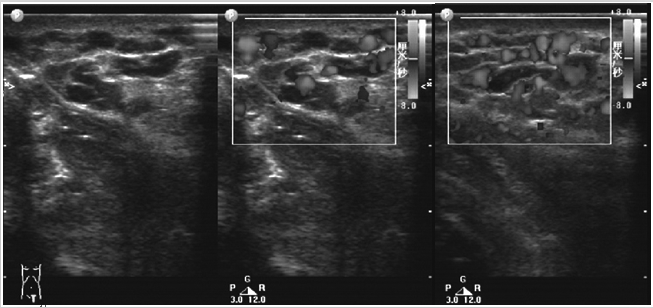

彩色多普勒超声在体表海绵状血管瘤中的诊断价

653x308 - 160KB - PNG